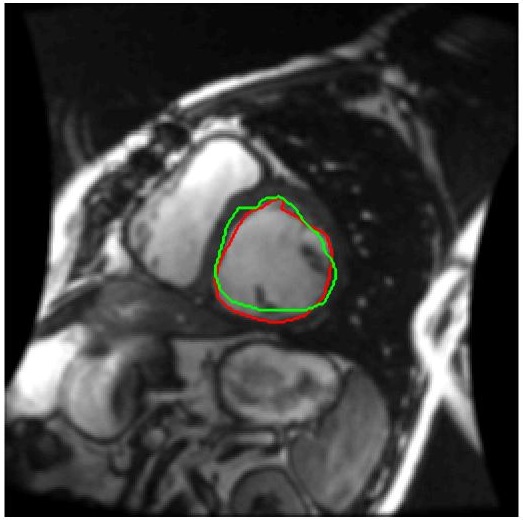

We train our ISR network from scratch. Each volume slice is treated as a separate image and transformed by random rotation and translation. We rotate the images between in steps of . For each rotation we translate the image by pixels in steps of . Thus on an average we get transformation for each image. Thus an average of slices per image gives a total of cardiac MR images. We show results on ISR for scale factor . Results for ISR are summarized in Tables 5. Following the approach for retinal landmark and pathology segmentation, we also show results for cardiac left ventricle segmentation (Table 6). For each segmentation approach we employ UNets as the segmentation framework and show results for different super-resolution methods as well as the low-resolution images (). Dice metric values for segmentation accuracy are shown in each case. Similar to retinal pathology segmentation we extract a patch covering the pathology and apply super-resolution for scale factors .

Figure 6 shows results for segmenting the cardiac LV from MRI. For each case we present results on the original HR images, SR images obtained by each of the methods being compared and also when using the LR images (scale factor ). It is quite obvious that the LR images are very fuzzy and don’t give accurate information on the anatomical boundaries. On the other hand the SR images from our method can predict a highly accurate reconstruction of the actual image. Other ISR methods show some degree of blur in the SR images. It is remarkable that deep neural network based methods are able to reconstruct original high quality images despite limited information in LR images. This is possible because of the ability of the generator networks to learn the relation between HR and LR images.